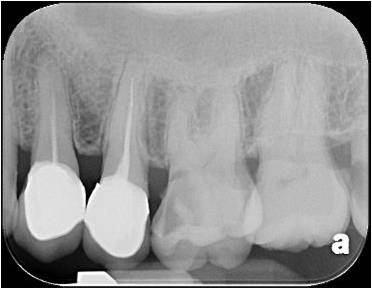

顯微根管治療

鑄造金屬釘柱